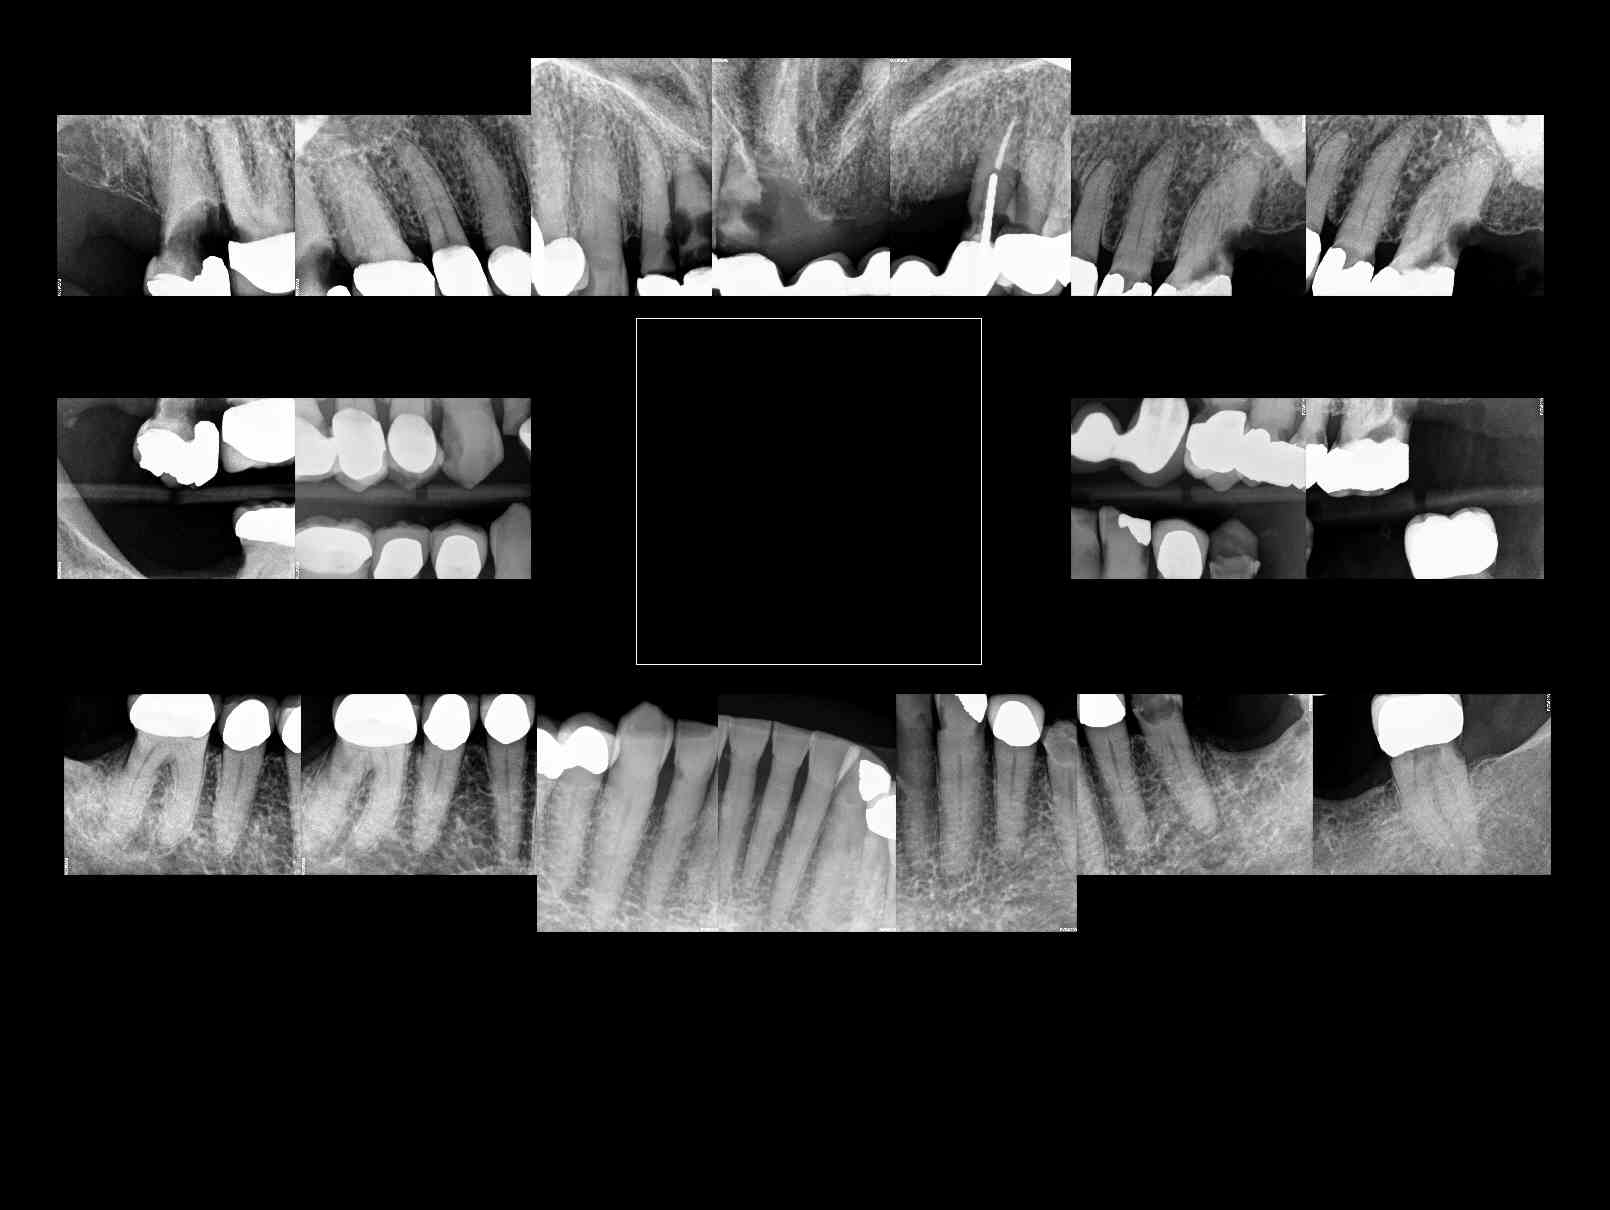

Dental Auction No. 10695: All on 4, maxillary & mandibular arches

Patient requests ALL ON 4 for both upper and lower arches, complete case fee. X-rays available, taken last week